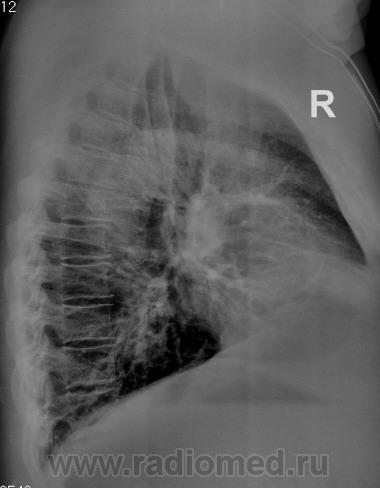

Первое, что напрашивается почти автоматически, массивные плевральные наслоения справа в передне-медиальном отделе.

А, если травма, если перелом ребра, даже если был плеврит и образовалась шварты,  против чего совершенно не возражаю, то почему так "нагло-интеллегентно" смотрится на "прямой рентгенограмме косто-диафрагмальный синус? А сердечно-диафрагмальный пострадал?

Ну уж не такой-уж "нагло-интеллегентно", а в боковай и особенно в задних отделах спайки.

Ну, а в передних отделах, по "боковой", вообще синуса, как такового не видно?

абдоминальный жир через диафрагму лезит...но как-то многовато...

Было сделано КТ. Было подтверждено то, что ранее называлось медиастинальной липомой.

Да, нет, Вы совершенно правы, в последнее время все реже пользуются термином "медиастинальная липома", все чаще приходится слышать - околосердечная жировая подушка или другие варианты.

Мне первое, что приходит в голову - медиастинальный липоматоз.

Когда я только начинал работать рентгенологом, такие изменения на снимке в области правого кардиодиафрагмального синуса - всегда вгоняли меня в некий ступор - "это" дело накладывалось на тень сердца на боковой рентгенограмме, и чего только я не подозревал: и плевральные наложения,  и осумкованную жидкость, и даже ателектазы Однако, благо, на КТ реконструируя Р- снимки (есть такая функция в совр. КТ) - я очень часто убеждался, что все изменения вызванны именно околосердечной жировой подушкой (за границей "fat pad"). Обычно это довольно тучные люди, с хорошо развитой жировой прослойкой. И такие изменения встречаются очень часто и никакая это не липома. Ставить медиастинальный липоматоз, на мой взгляд, по таким изменениям тоже не верно. Мы же не ставим на КТ ОБП - ожирение: видя большое количество жира в БП (а его там тоже хватает и по брыжейкам, и по сальнику).

А по поводу снимков, теперь я более критично отношусь к изменениям в этой области: правда на этом фоне можно и пропустить чего...

Нам, довольно большое подспорье, именно, в таких случаях, оказывает боковая линейная томография (используем, то, что имеем).